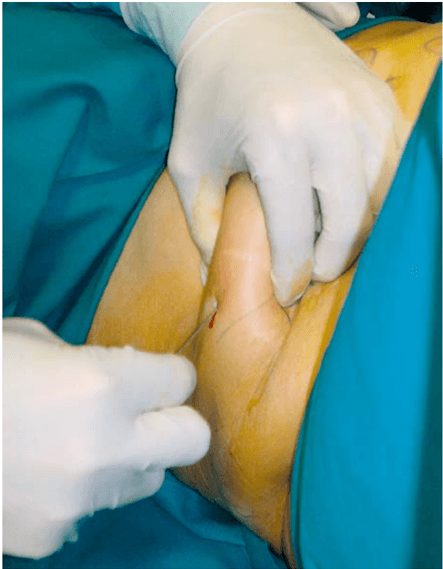

Stemming the Leak: A Novel Treatment for Gastro-Bronchial Fistula

F. M. Mongardini, C. Cacciatore, A. Catauro, F. Maglione, F. Picardi, A. Lauro, C. Gambardella, A. Allaria, L. Docimo, Digestive Diseases and Sciences, 2022